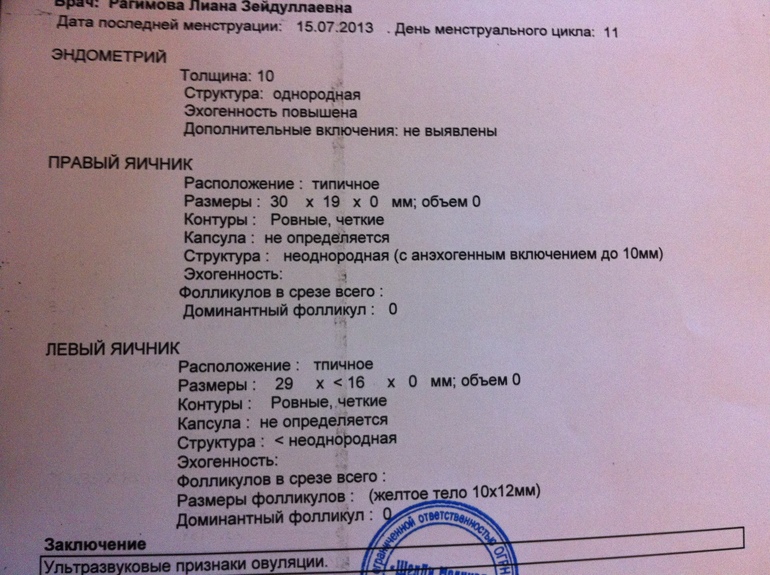

Созревание фолликула в яичнике: этапы и процессы